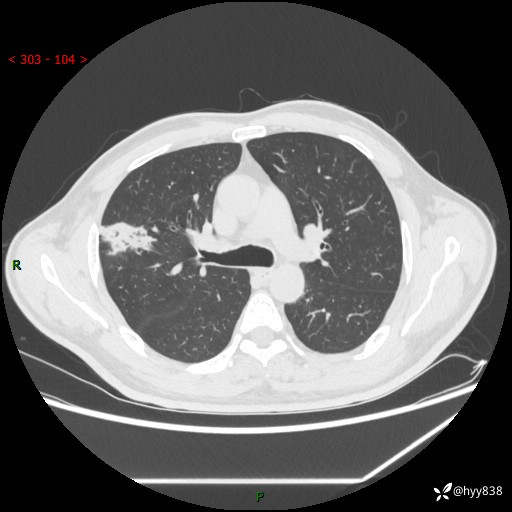

现病史:患者2天前体检完善胸部CT提示:右上肺团块影,炎症可能,肿瘤性病变不除外,冠状动脉钙化,无咳嗽、咳痰,无寒战发热,无恶心、呕吐等其他特殊不适,未予以特殊治疗,现为明确病变性质来我院就诊,门诊以“肺肿物性质待查”收入我科。 起病以来,患者精神、饮食、睡眠可,大小便正常,体力体重较前无明显变化。

胸部CT平扫+增强